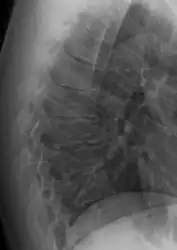

Scheuermann's disease on lateral CT of the T spine

Scheuermann's disease on lateral Xray of the T spine

Diagnosis is typically by medical imaging. The degree of kyphosis can be measured by Cobb's angle and sagittal balance.